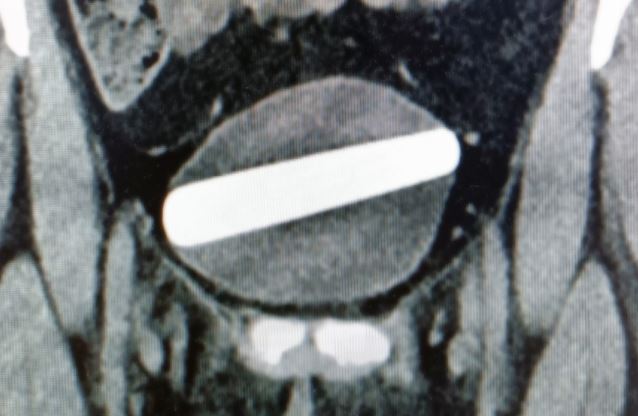

Wer in einer urologischen Notaufnahme arbeitet, erlebt so manche Überraschung - so auch das Personal einer Klinik in Israel [Noyman Y et al. Urol Case Rep 2023;47: 102349]. Eine 29-Jährige hatte sich zur sexuellen Stimulation einen Dildo in die Harnröhre eingeführt und ihn dabei versehentlich ganz in die Harnblase geschoben. Mit einer Dysurie und Schmerzen erschien sie in der Notaufnahme, sonst war sie beschwerdefrei. Erst im Ultraschall und in der Computertomografie zeigte sich ein 9 × 2,5 cm großer Fremdkörper.

CT-Scan der Blase, in der Breite gänzlich ausgefüllt durch den Fremdkörper

© Noyman Y et al. Urol Case Rep 2023;47:102349